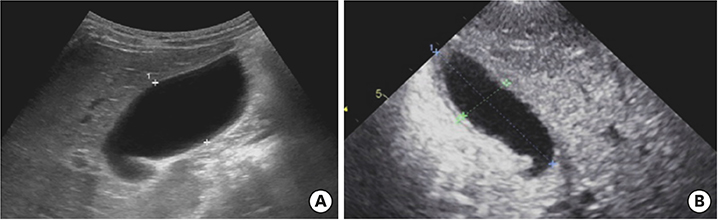

After discharge and 23 days of fever onset, a follow-up abdominal sonography revealed a slower regression of the GB hydrops (Fig. 5A). Echocardiography performed at 81 days after onset of fever revealed complete improvement of both the coronary artery lesion and GB hydrops (Fig. 5B).

Fig. 5

Abdominal ultrasonography (A) performed at 23 days after fever onset revealed a slow regression of the gallbladder hydrops (6.7×3.2 cm in size). Echocardiography (B) performed at 81 days after fever onset revealed a complete improvement in gallbladder hydrops and a normal gallbladder.